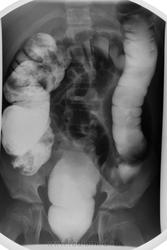

Долихосигма, и плохо очищенная толстая кишка. В детской патологии не силён.

Долихомегасигма, я б сказала, что объясняет клинику запоров. Впрочем, вся кишка расширена. Зоны аганглиоза не видно, на Гиршпрунга не похоже. Селезеночный изгиб не показан адекватно, так что со снимками лежа судить о наличии болезни Пайра проблематично, да и клиники не дано, а жаль.